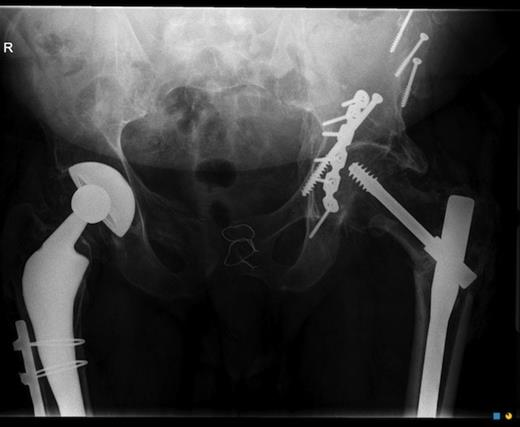

He presented at the age of 19 to the emergency department after a motorcycle accident with a fractured pelvis, requiring fixation by wiring of the pubic symphysis and open reduction and internal fixation of the left acetabulum via a trochanteric osteotomy side approach(Fig. 1). He had previously experienced similar trauma, where he suffered a right hip fracture and trauma to the bowel, requiring a right total hip replacement and reparative bowel surgery, respectively.

X-ray of the pelvis showing the wiring of the pubic symphysis, internal fixation of the left acetabulum and right total hip replacement